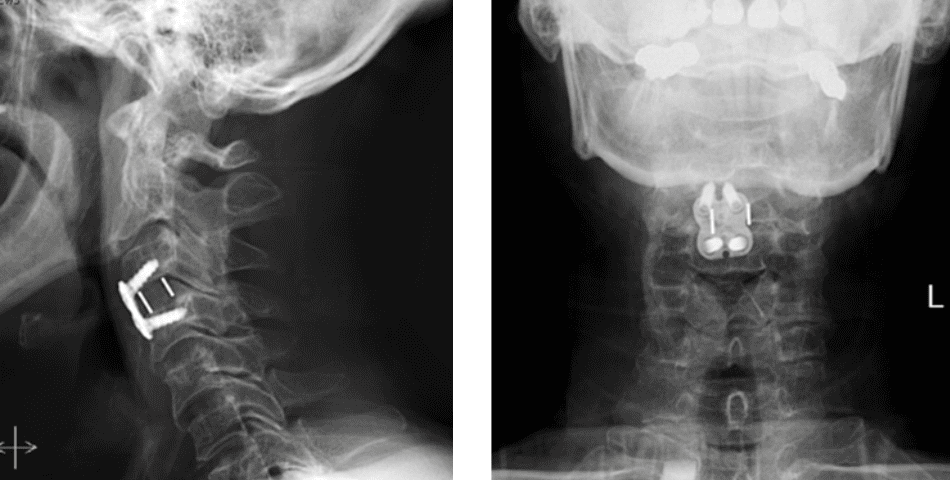

Figure 2. Lateral and AP cervical spine x-rays s/p ACDF

Dr. Imani performed an Anterior Cervical Discectomy and Fusion to remove the pressure of the herniated disc from compressing the spinal cord and stabilizing the spinal column with a fusion of the C3/C4 disc space.

After Dr. Imani’s surgery, the patient is making a full recovery. He is able to walk and move both arms/hands.